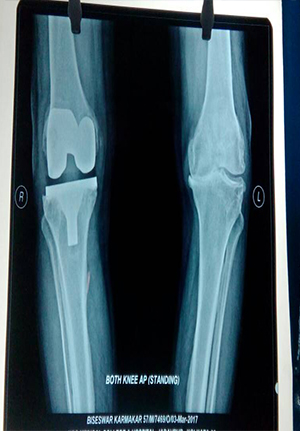

Total Knee Replacement

Total knee replacement in general is a very good operation for relieving pain.